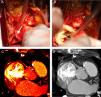

Case reportA 56‐year‐old woman, with a history of hypertension, hypothyroidism and anxiety attacks, was seen in the emergency department for constricting chest pain, non‐radiating, and dyspnea, that began during a water exercise session and subsided after 20 minutes’ rest. She reported similar episodes in the past but of shorter duration, always triggered by exercise, particularly swimming. The electrocardiogram revealed no significant alterations, but laboratory tests showed slight elevation of myocardial necrosis markers. The patient was admitted with a diagnosis of non‐ST elevation acute coronary syndrome. Transthoracic echocardiography revealed good biventricular systolic function, with no regional wall motion abnormalities. Cardiac catheterization showed right dominance, no significant stenosis, and the right coronary artery (RCA) originating from the lateral wall of the ascending aorta, above the sinuses of Valsalva (Figure 1), potentially being compressed between the aorta and the pulmonary artery. Exercise testing documented ischemia (Figure 2A). Coronary CT angiography revealed the RCA originating between the left anterolateral aortic wall and the ascending portion of the pulmonary artery, its proximal segment describing a convoluted course parallel to the aorta and close to the pulmonary artery (Figure 3). The patient was diagnosed with myocardial ischemia due to anomalous origin of the RCA and was referred for surgical revascularization. While awaiting surgery, she continued to suffer recurrent anginal episodes despite optimal anti‐ischemia therapy. Surgical inspection confirmed that the RCA originated in the left anterolateral wall of the ascending aorta, above the sinuses of Valsalva, with an extramural and interarterial course, and latero‐lateral anastomosis of the RCA to the anterior aortic wall was performed (Figure 4A). Postoperative exercise testing documented no ischemia (Figure 2B). Repeat coronary CT angiography (Figure 4B and C) showed a good surgical result. Fifteen months after surgery, the patient is asymptomatic, with no recurrence of angina.

(A): Surgical dissection of the emergence of the right coronary artery showing its origin in the left anterolateral aortic wall and an extramural and interarterial course; (B): following transection of the aorta, the origin is shown to be above the sinus of Valsalva, posterior to the commissure separating the right and left cuspids (note the angle of the coronary ostium); (C) and (D): multislice computed tomography multiplanar reconstruction following surgical revascularization, showing latero‐lateral anastomosis (arrows). The high‐density images correspond to surgical clips.

In the present case, given the high origin and extramural course of the RCA (Figure 4A), reimplantation would have resulted in an acute angle in its initial course or an even higher abnormal implantation; it was thus decided to perform latero‐lateral anastomosis to the anterior aortic wall, with good clinical results and ischemia test.